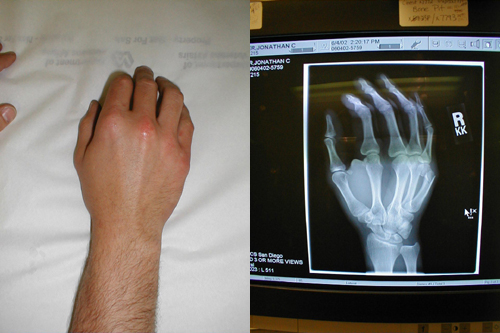

كسر Boxer في اليد اليمنى

لاحظ وجود التوذم على سطح اليد اليمنى الظهري ، و أكثر ما يبدو أسفل الإصبع الصغرى . هذه الحالة سببها كسر في السنع الخامس ( وهو العظم الذي يقع أسفل الإصبع الصغرى ) ، غالباً يترافق مع ضرب جسم ما مع كون القبضة مغلقة . و يبدو في صورة الأشعة السينية وجود كسر في السنع البعيد لليد اليمنى.